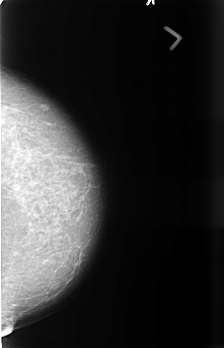

B_3441_1.LEFT_MLO

B_3441_1.LEFT_CC

LEFT_MLO LINES 4488 PIXELS_PER_LINE 2912 BITS_PER_PIXEL 12 RESOLUTION 50 NON_OVERLAY